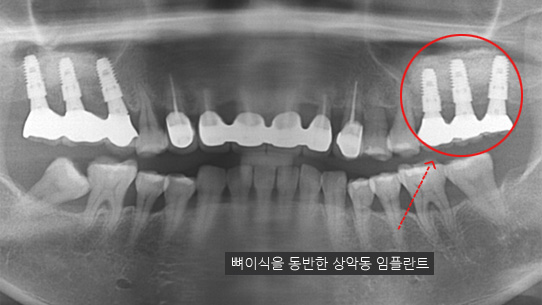

위 턱뼈는 아래턱뼈보다 얇고 코와 뺨 사이 빈 공간(상악동)이 있어서 임플란트를 식립할 경우 실패 가능성이 높아집니다.

상악동거상술이란 임플란트 수술방법을 시행할 때 노하우가 부족하면 임플란트 식립 후 임플란트가 빠져버리거나 입 천장 쪽에 구멍(천공)이 나는 부작용이

생기기 때문에 치과치료 중 가장 어려운 수술 중 하나 입니다.

고운미소치과 문원규박사는 턱뼈의 해부학적 구조를 충분히 고려하고 임플란트 수술을 해온 노하우를 바탕으로 상악동 거상술은

물론 난이도가 높은 수술을 안정적으로 진행하고 있습니다.